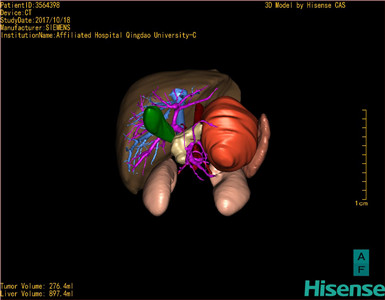

胰腺实性假乳头状瘤-CH-001-N-001499

CT结果输入海信CAS系统后行3D重建及手术规划后,于2017-10-19全麻下行“胰体尾肿物切除术+脾切除术+大网膜切除术”手术治疗:

术前三维重建及手术方案设计:

将0.625mm双源薄层CT资料的静脉期和动脉期Dicom格式文件导入海信CAS系统。

通过调节窗宽窗位调整CT序号,对肝实质,胆囊,下腔静脉,肿瘤,肝动脉、门静脉及肝静脉等进行三维重建;系统自动计算肝脏体积。

模拟手术操作,自动计算切除肿瘤体积。肝脏体积为453.7ml,通过比对2-3岁正常肝脏体积为475.97±99.7ml,通过术前模拟手术,精准判断切除后剩余肝脏体积能耐受,避免肝衰竭发生。

术前三维重建:

重建图片